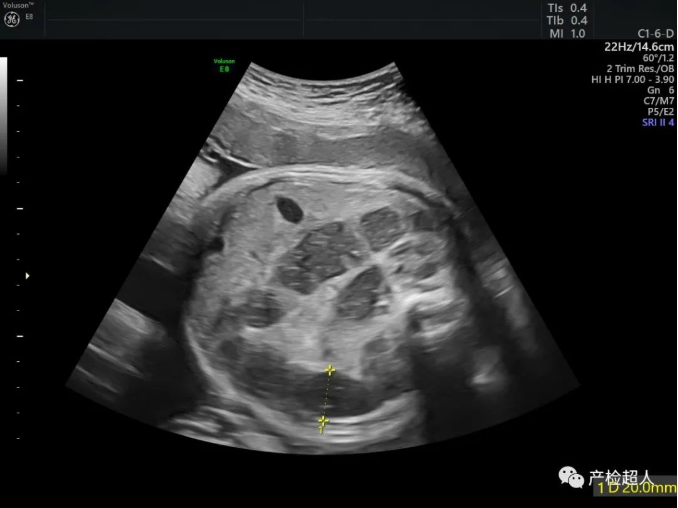

擅长:熟练掌握腹部、成人心脏、血管、浅表器官、关节、妇科、胃肠造影的超声检查,尤其擅长产科以及儿科检查,近15年主要从事产科胎儿畸形的研究,对产前诊断、胎儿宫内发育不同阶段畸形的检测、产后康复及妇产科常见病、疑难病的超声诊断技术娴熟。